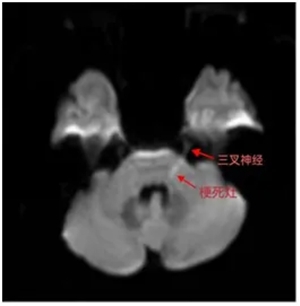

颅脑MRI显示:左侧桥脑线样梗死灶(箭头处),病灶紧邻三叉神经纤维!原来:

三叉神经感觉纤维受损→产生"牙龈肿胀"错觉

自主神经纤维受累→引发血管神经性水肿